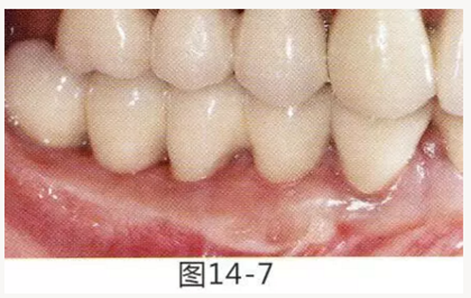

7.png

圖14-7  配戴最終修復(fù)體完成5年后的狀態(tài)。保持良好。